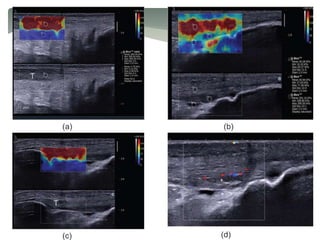

(a) (b)

(c) (d)

(a, b) Longitudinal and (c, d) transverse free-hand strain elastograms of the

middle third of asymptomatic Achilles tendons (T) showing the two distinct

ultrasound elastography patterns of normal tendons.

Type 1 (a, c) tendons appear homogeneously stiff, (green/blue) with no distinct

soft (red) areas.

Type 2 (b, d) tendons appear considerably inhomogeneous with soft (red) areas

(longitudinal bands or spots), which did not correspond to any changes in B-

mode ultrasound.

The retro- Achilles fat appears as a mosaic of green, red and blue. Note the red

areas at the lateral and medial sides of the tendon in the transverse plane (c, d),

corresponding to an artefact, secondary to difficulty in stabilising the hand-held

transducer.